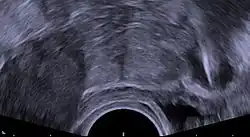

Insertion

A copper IUD can be inserted at any phase of the menstrual cycle, as long as pregnancy can be reliably excluded. It may be inserted in the immediate postpartum period (shortly after delivery of the placenta), and after an induced medical, surgical, or spontaneous abortion provided a genital tract infection can be reliably excluded.[25][11][39][5][24] NSAIDs taken prior to the procedure and use of local anesthesia are recommended to reduce pain at the time of insertion.[15][40][29]